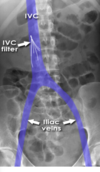

**What is the artifact shown in this image?** **What pathology does it reduce the risk of?** Naso-jejunal tube Colonic stent Pig-tail (JJ) stent Percutaneous nephrostomy tube Inferior vena cava (IVC) filter

**Inferior vena cava (IVC) filter** An IVC filter may be used to reduce the risk of large pulmonary emboli